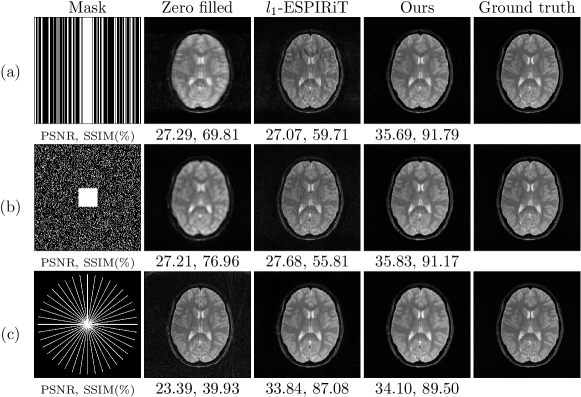

Reconstruction and comparisons: The proposed method in Equation 6 was implemented with Python. We performed l1subscript𝑙1l_{1}-ESPIRIT (regularization parameter=0.005) reconstruction with the BART toolbox [9, 10]. The coil sensitivity map was estimated from a 20×\times20 calibration region in the central k-space using ESPIRiT. To compare the images reconstructed using different methods, we calculated the peak signal-to-noise ratio (PSNR) and structural similarity index measure (SSIM) with respect to ground truth. Also, we validated the proposed method in different acquisition settings such as acceleration along one dimension, two dimensions, or radial acquisition. The metrics of different reconstructions were shown in Table 1. Generally, the result demonstrated that the proposed method could restore the high-quality MRI with both high acceleration factor (i.e., 20% samples) and high PSNR (i.e., >>35 dB). Figure 2 shows the comparison between l1subscript𝑙1l_{1}-ESPIRIT and the proposed method.

Refer to caption

Figure 2: Row (a) shows the proposed method can remove the aliasing artifacts along phase encoding direction in the case of using 30% k-space. Row (b) shows the proposed method can eliminate the burring fog on the image in the case of using 20% k-space. Row (c) shows the two methods’ performances were close. With 40 radial spokes acquired in k-space.